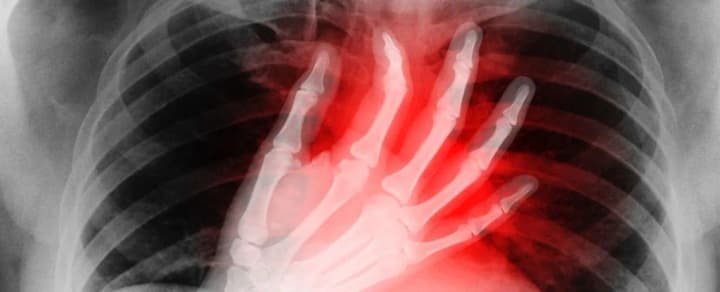

In addition to irregular and rapid heartbeat, people may experience dizziness or shortness of breath. Sometimes the symptoms become so severe that people are forced to seek medical attention. In general, according to the researchers, this is atrial arrhythmia caused by alcohol consumption.

The authors of the article emphasize that alcohol, by affecting the nervous system, can lead to dehydration and inflammation, which disrupts the normal functioning of the heart. Sometimes this can lead not only to changes in heart rate, but also to loss of consciousness.